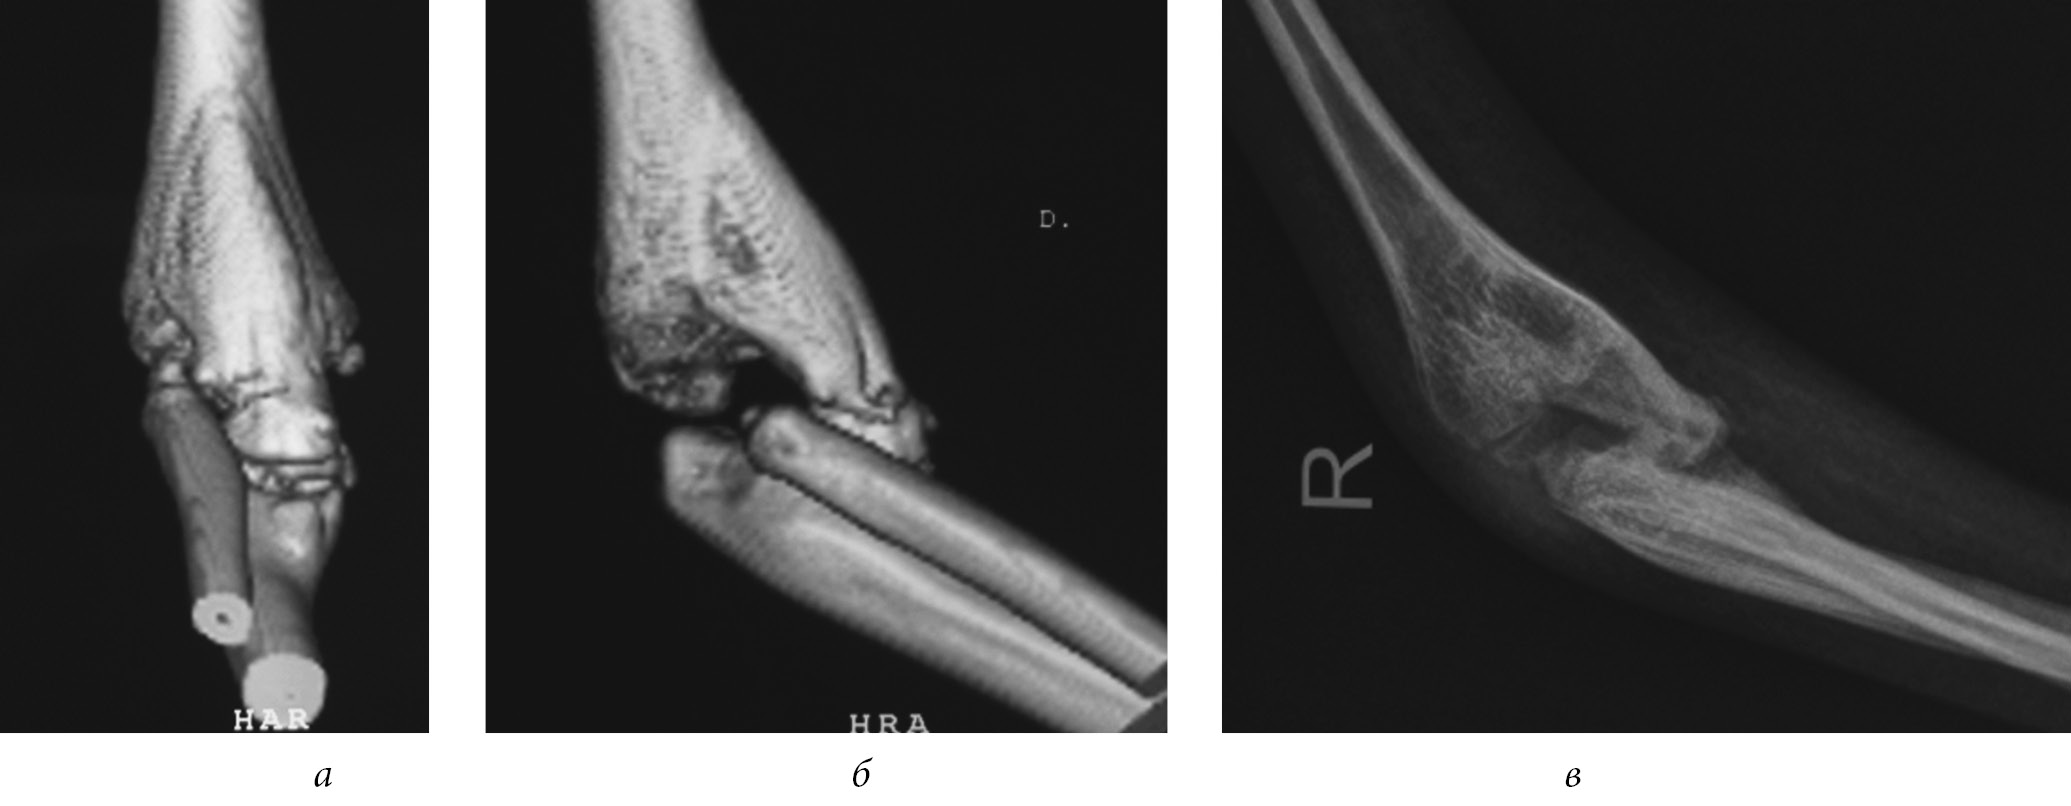

In 3.8% of patients, the elbow joint had ossified after posterior arthrolysis, which impeded flexion and extension of the elbow joint. In 2 cases, after repeated arthrolysis, the ossifications recurred, and one year after the surgery the movements became oscillating, and then ankylosis appeared at an angle of 100° (Fig. 4). Only in 1.8% of patients after repeated arthrolysis of the elbow joint and removal of ossification, was it possible to obtain the range of passive movements within 56.2 ± 3.7° at the elbow joint.

Fig. 4. Ossification of the elbow joint on the front surface of patient B., 5 years of age, after posterior arthrolysis of the elbow joint: a — computed tomography of the elbow joint, frontal view; b — computed tomography of the elbow joint, lateral view; c — a radiograohic image of an elbow joint in a lateral view